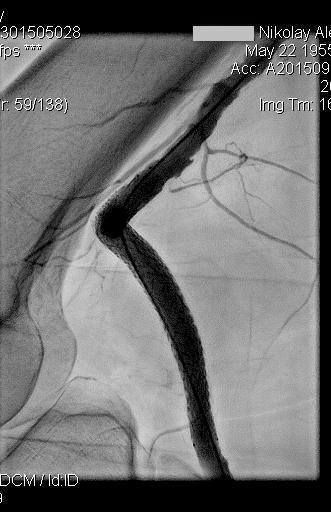

16 июня 2016 года в ЦЭЛТ, в отделении сердечно-сосудистой хирургии, состоится семинар и вебинар по самым актуальным вопросам интервенционной кардиологии и ангиологии на тему: «Современные подходы лечения пациентов со сложными поражениями артерий нижних конечностей».

В программе мероприятия: демонстрация эндоваскулярных операций в прямом эфире, лекционная часть и обсуждения докладов.